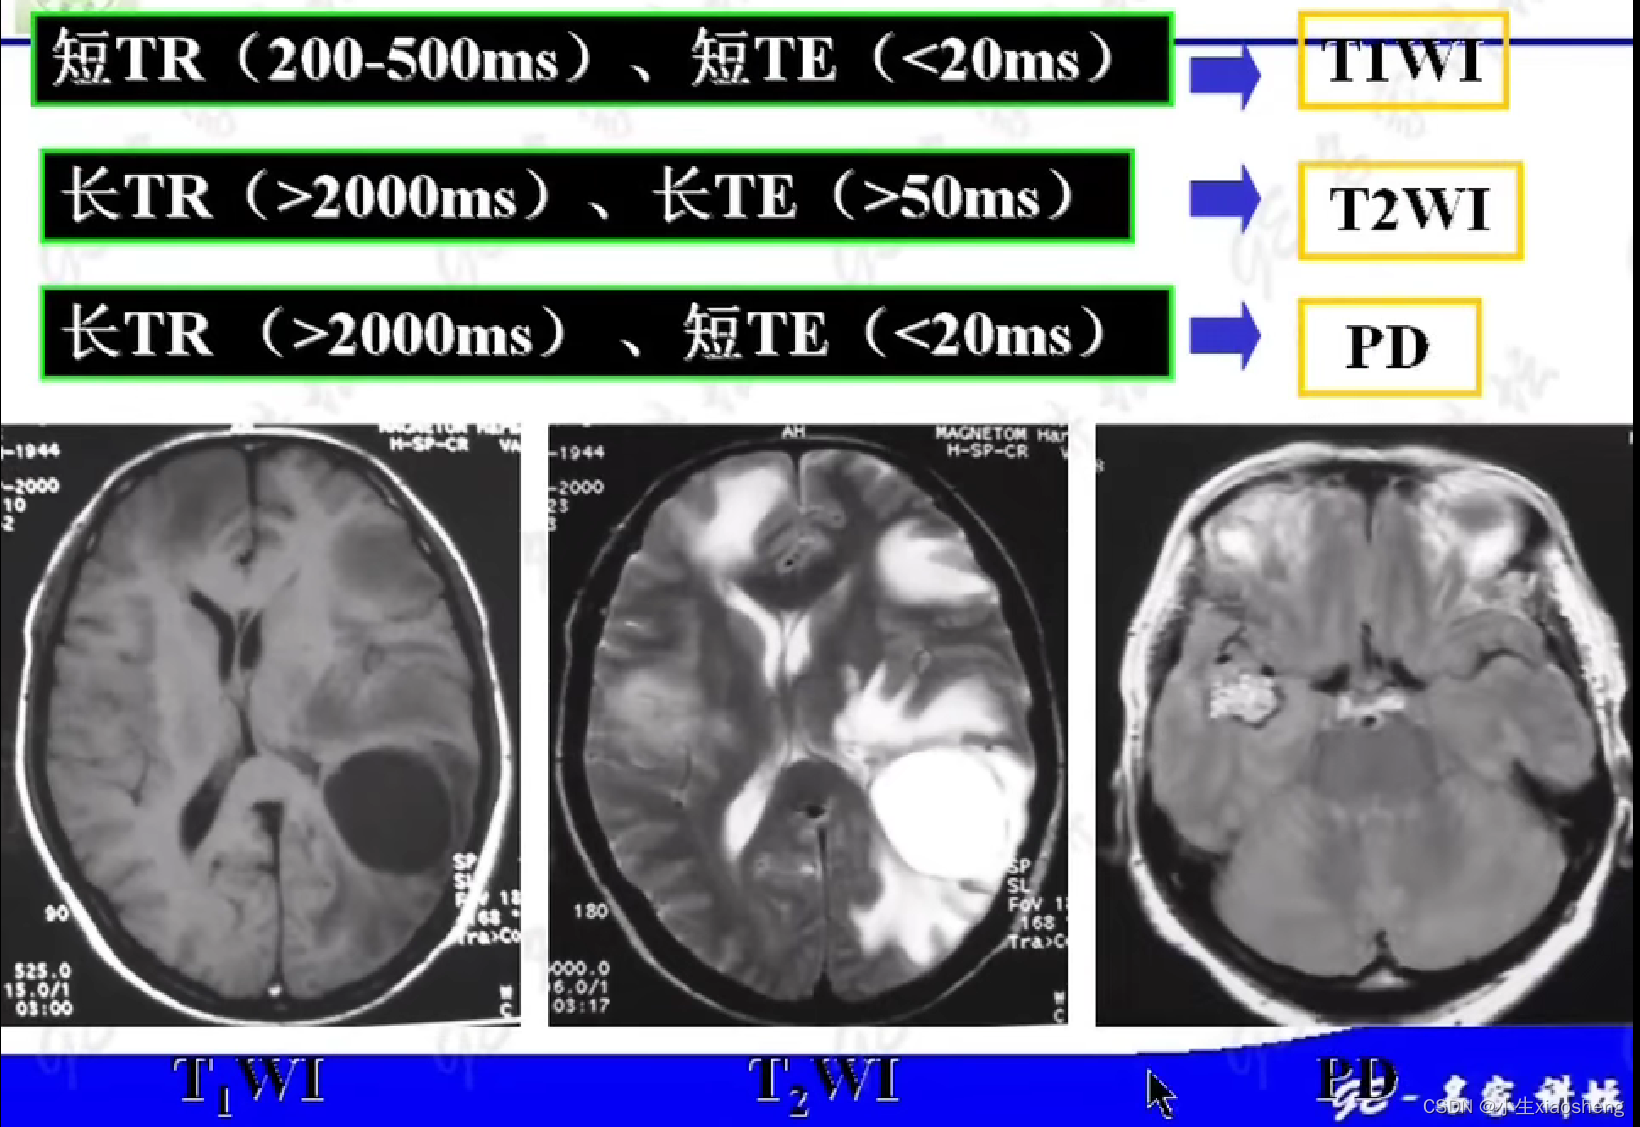

选择合适长的TE获得最好的T2对比:一般TE选择两种组织生物T2值附近可获得最好的T2对比。

选择合适短的TR获得最好的T1对比:一般TR选择两种组织生物T1值附近可获得最好的T1对比。